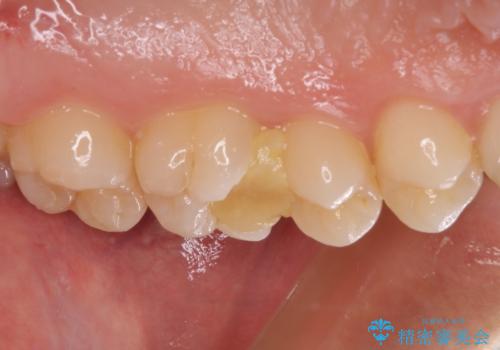

処置開始前から神経組織を部分的に除去する可能性が高いことが分かっていたため、ラバーダムなどの環境を整え、無菌的環境下にて処置を進めて行きました。

虫歯は深くまで進行しており、歯冠部の神経から出血が認められました。神経を部分的に除去したところ出血が治まったので、生体親和性の非常に高いセメントにて充填し、仮封をしました。

後日状態を確認したところ、残された神経に異常がなかったため、セラミッククラウンにて補綴治療を行いました。